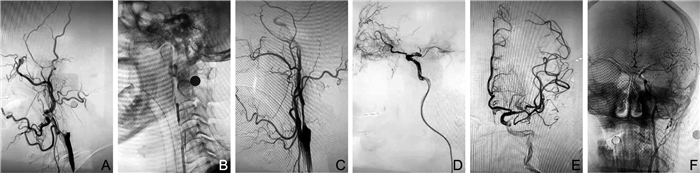

Analysis of safety and efficacy of emergent carotid artery stenting in patients with acute anterior circulation stroke with tandem lesion treated with mechanical thrombectomy

ZHANG Dong-huan, LIU Yi-feng, KANG Mei-juan, WANG Ning, SUN Jun, WEN Chang-ming

2022, 20(7): 1143-1146. doi: 10.16766/j.cnki.issn.1674-4152.002543

Objective  To explore the treatment options of mechanical thrombectomy for extracranial carotid artery lesions in patients with acute anterior circulation tandem occlusion stroke, and to evaluate its efficacy and safety.  Methods  From January 2018 to December 2019, 18 patients with acute tandem occlusion of the extracranial internal carotid artery and intracranial large artery were admitted to Department of Neurology, Nanyang City Central Hospital and treated by endovascular treatment. There were 9 males and 9 females, aged 60 to 70 years old. According to different treatment methods, 18 patients were divided into emergency stent group (11 cases) and emergency non-stent group (7 cases). The immediate intraoperative recanalization of blood vessels during the operation was judged according to the classification of cerebral infarction thrombolysis (mTICI), and the 90-day modified Rankin Scale (mRS) score of 0-2 was defined as a good clinical prognosis.  Results  There was no statistically significant difference in clinical baseline data such as age, gender distribution, preoperative National Institutes of Health Stroke Scale (NIHSS) score, preoperative Alberta stroke project early CT (ASPECT) score, etiology classification, treatment method, lesion type, blood vessel occlusion site in two groups (all P > 0.05). The rates of successful recanalization of blood vessels (mTICI class 2b-3) of the emergency stent group and emergency non-stent group was 72.7% and 71.4%, respectively; however, there was no statistically significant difference (P > 0.05). The rates of symptomatic intracranial hemorrhage were 9.1% and 0, respectively. Also, there was no statistically significant difference (P > 0.05). There was no statistically significant difference in the modified mRS score and 90-day mortality between the two groups of patients after 90 days (all P > 0.05). The difference in the residual stenosis rate between the two groups was statistically significant (P < 0.05).  Conclusion  In the endovascular treatment of acute anterior circulation tandem occlusion, emergency extracranial carotid artery stenting may be effective and safe.